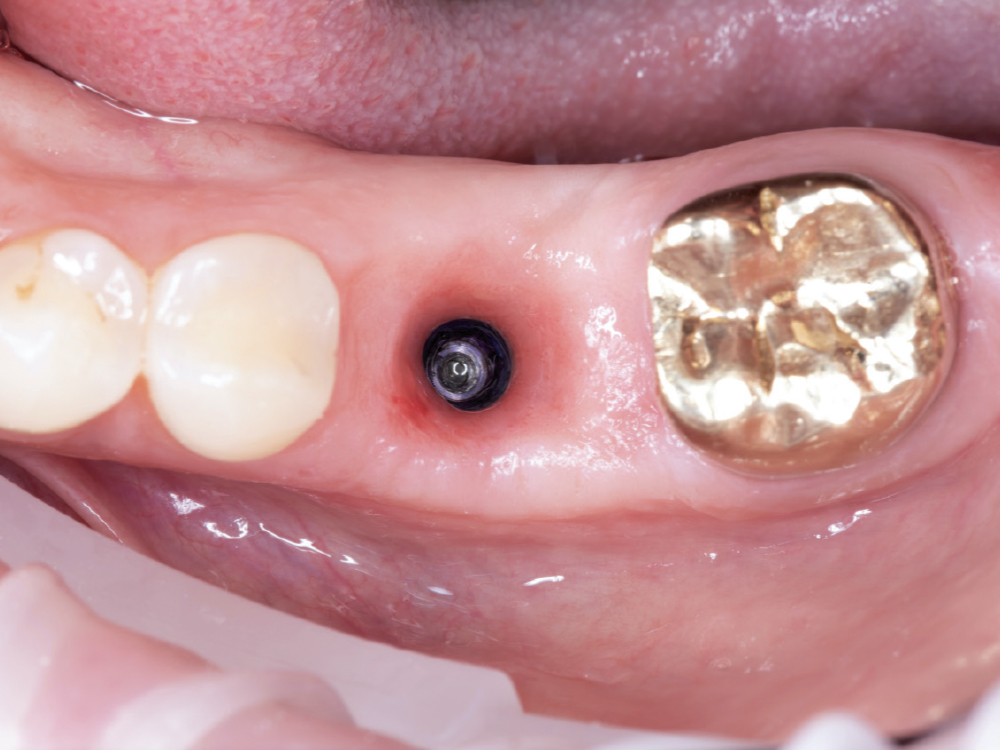

Capture the Surrounding Soft Tissue Immediately

Capture the Surrounding Soft Tissue Immediately. Scan the peri-implant soft-tissue architecture as soon as the scan body is placed, before the tissue collapse occurs. Gingival tissues begin to collapse and distort within minutes of scan body insertion, and the initial tissue contours are critical for creating proper emergence profiles. Work efficiently but thoroughly to document the tissue topography in its most accurate state.

Implant post in socket

Finished Implant Restoration